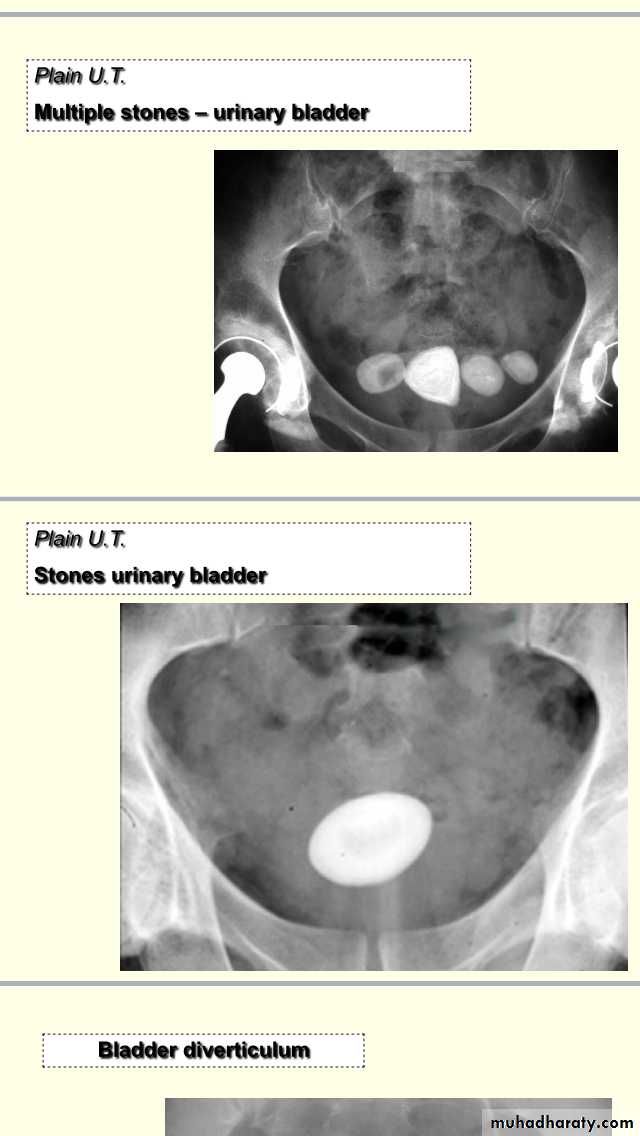

Description :-Xray of pelvis (NOT KUB),show multiple radiopaque shadow, rounded shape smooth surface,above pubis 2.5cm size.what you recognize from the picture ?Old age pt ,bedridden for long time,due to OA changes,,he may be taken VIT D supplements ,he may have BPH.

Radiopaque shadow ,smooth ,round surface,(2,5cm)size,solitary.Management of vesical stone:-if no underlying UT pathology ,Rx depend on the size,in pediatric age group by open surgery,in adult:endoscopic Mx,if >3cm cystolithotomy,if 2.5cm endoscopic crushing(cystolithopaxy) or equalIVU cystogram phase :-showing opacity with thickening and irregular of bladder wall(outline) due to neurogenic bladder (multiple saccule in the bladder commonly seen +trabeculation) with diverticulum (paraureteric buldging).